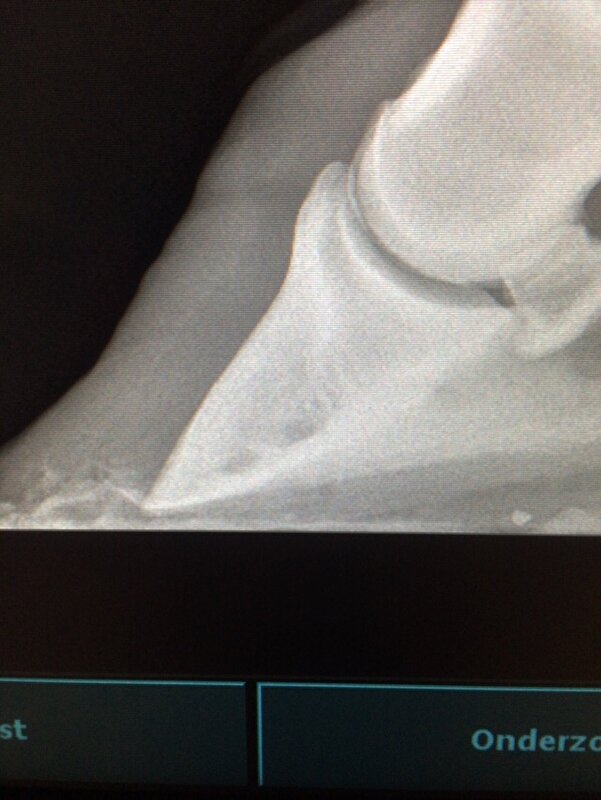

Dus volgens mij werkt het. nuvel schreef:Had gister gebeld maar er was nog niks klaar. Net heb ik de foto's gekregen van beide voorvoeten en het ziet er niet zo goed uit. Beide hoefbenen zijn gekanteld. De ene als je er voor staat is het het linker voorbeen daar komt het hoefbeen bijna door de zool. Als je er voor staat het rechter voorbeen heeft nog een cm voor hij door de zool komt.

Zal straks de rontgenfoto's en foto van het paard hier plaatsen. Ga ze nu eerst naar de kliniek sturen want wil er voor vechten. Dit paard is te sterk en te vrolijk om nu de handdoek in de ring te gooien. Ze staat op dubbele pijnstiller om nu niet te hoeven lijden.